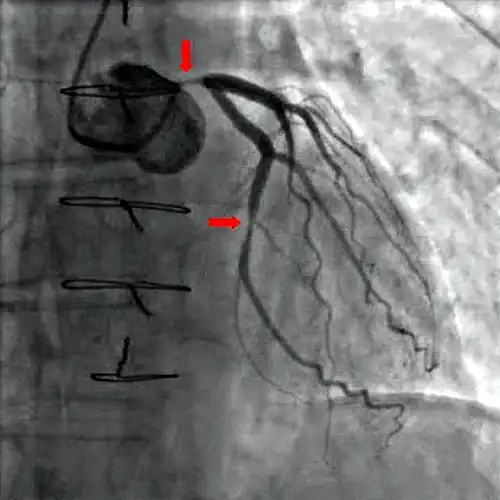

Koronarangiographie und Ventrikulographie

Mit Hilfe der diagnostischen Koronarangiographie können Koronararterien dargestellt und deren Anatomie sowie das Ausmaß und die Lokalisation eventueller Stenosen beurteilt werden. Sie ist die Untersuchung mit der besten Aussagekraft. Bei dieser Untersuchung wird ein Herzkatheter über die Arteria femoralis (Oberschenkelarterie) oder seltener über die Arteria brachialis (Oberarmarterie) bis zu den Abgängen der Koronararterien aus der Aorta vorgeschoben und Kontrastmittel in die Abgänge injiziert. Mit Hilfe von Röntgenstrahlung können die Koronararterien sichtbar gemacht und beurteilt werden.[24] Der Katheter kann, unter Überbrückung der Aortenklappe, weiter in die linke Herzkammer vorgeschoben werden. Diese Untersuchung wird als Ventrikulografie bezeichnet. Sie ermöglicht zusätzlich regionale Kontraktionsstörungen sichtbar zu machen, die zum Beispiel Hinweise auf zurückliegende Herzinfarkte bieten können, sowie eine Beurteilung der linksventrikulären Pumpfunktion über Berechnung der Auswurffraktion und die Bestimmung der Dehnbarkeit der Herzmuskulatur (Compliance) durch Bestimmung des enddiastolischen Volumens.[1]

Da es sich bei der Koronarangiographie und der Ventrikuloangiografie um invasive Untersuchungsmethoden handelt, kann es neben relativ ungefährlichen Komplikationen (beispielsweise Hämatome an der Einstichstelle) in sehr seltenen Fällen zu schwerwiegenden lebensbedrohlichen Komplikationen kommen. Dazu gehören vor allem Herzinfarkte, Schlaganfall, Spaltungen (Dissektionen) der Gefäßwände, Herzrupturen, Luftembolien und Arrhythmien.[4] Die Letalität der Untersuchung liegt unter 1:100.[1]

Aufgrund der nicht völlig ausschließbaren Risiken für das Auftreten von Komplikationen, der Strahlenbelastung sowie der Belastung der Nieren durch das Röntgenkontrastmittel, sollte die Indikation der Koronarangiographie zur Diagnose einer chronischen KHK relativ streng gestellt und im Sinne einer Nutzen-Risikoanalyse abgewogen werden. Nach den Empfehlungen der nationalen Versorgungsleitlinie (NVL) sollte diese Untersuchung nur dann erfolgen, wenn entweder alle nicht-invasiven Untersuchungsmethoden ohne Ergebnis ausgeschöpft wurden und trotzdem die Verdachtsdiagnose chronische KHK wahrscheinlich ist, oder wenn der Patient von Revaskularisationsmaßnahmen profitieren könnte.[4] Bei der Abwägung spielen des Weiteren bestehende kardiovaskuläre Risikofaktoren, zurückliegende Herzinfarkte und andere bestehende Herz-Kreislauf-Erkrankungen, die Einschätzung der Lebensqualität durch den Patienten sowie der Schweregrad der stabilen Angina pectoris nach CCS-Klassifikation eine wichtige Rolle. Für Letztere gilt, dass bei einem CCS-Stadium < III sowie bei erfolgreicher konservativer Pharmakotherapie, normalerweise keine Indikation für eine erneute Koronarangiografie besteht.[4]

Als diagnostische und therapeutische Maßnahme gilt die Darstellung der Herzkranzgefäße mittels Koronarangiographie als Goldstandard in der Diagnostik. In derselben Sitzung ist es möglich, signifikante Engstellen durch eine Ballondilatation (Perkutane transluminale coronare Angioplastie, PTCA), ggf. kombiniert mit der Implantation eines Stents aufzudehnen.